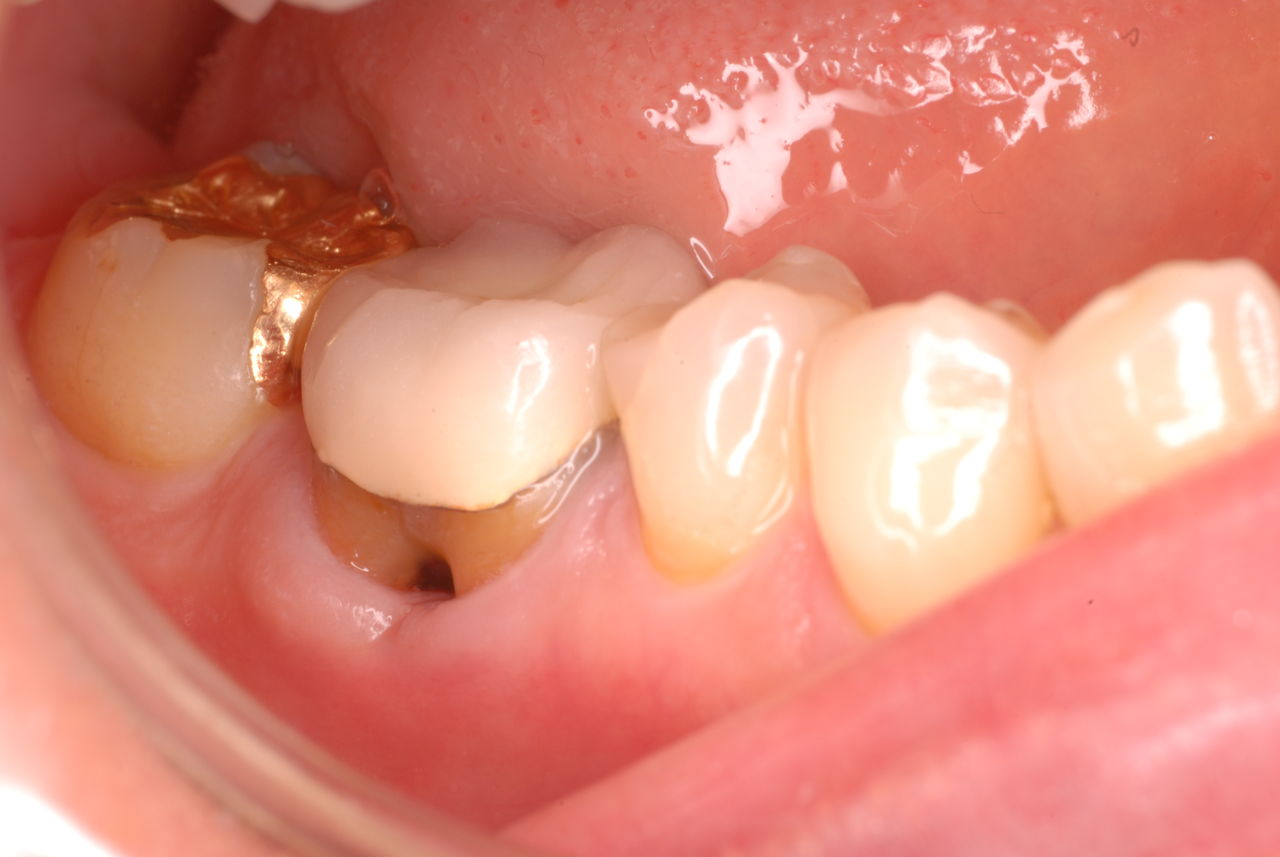

写真左下の親知らずが痛くなり抜歯しました。その後歯茎を除去して虫歯を露出させる処置を二回ほどしています。

レントゲンでは小さいですが、こう言う虫歯が一番怖いのです。

治療の成功率は極めて悪くすぐ再発しやすいのです。